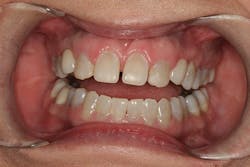

After approval of the diagnostic wax-up, profound anesthesia in the area of Nos. 6 through 11 was achieved (Septocaine, Septodont). Following sounding for bone to confirm adequate biologic width, laser soft-tissue recontouring in the areas of Nos. 6 through 11 was performed using an Er;Cr:YSGG soft- and hard-tissue laser (Waterlase, Biolase). Teeth Nos. 7, 8, 9, and 10 were prepared for conventional porcelain laminate veneers. Implant crowns were sectioned and removed from Nos. 6 and 11 (figure 4). To verify the radiographic implant identification, the abutments were removed and impression copings were tried in and radiographic seat was confirmed. The abutments were then replaced to serve as provisional restorative components. Screw access holes were blocked out and the provisional stent was used to fabricate provisional restorations on Nos. 6 through 11 (Luxatemp Ultra BL, DMG America) (figures 5, 6).

Figure 4